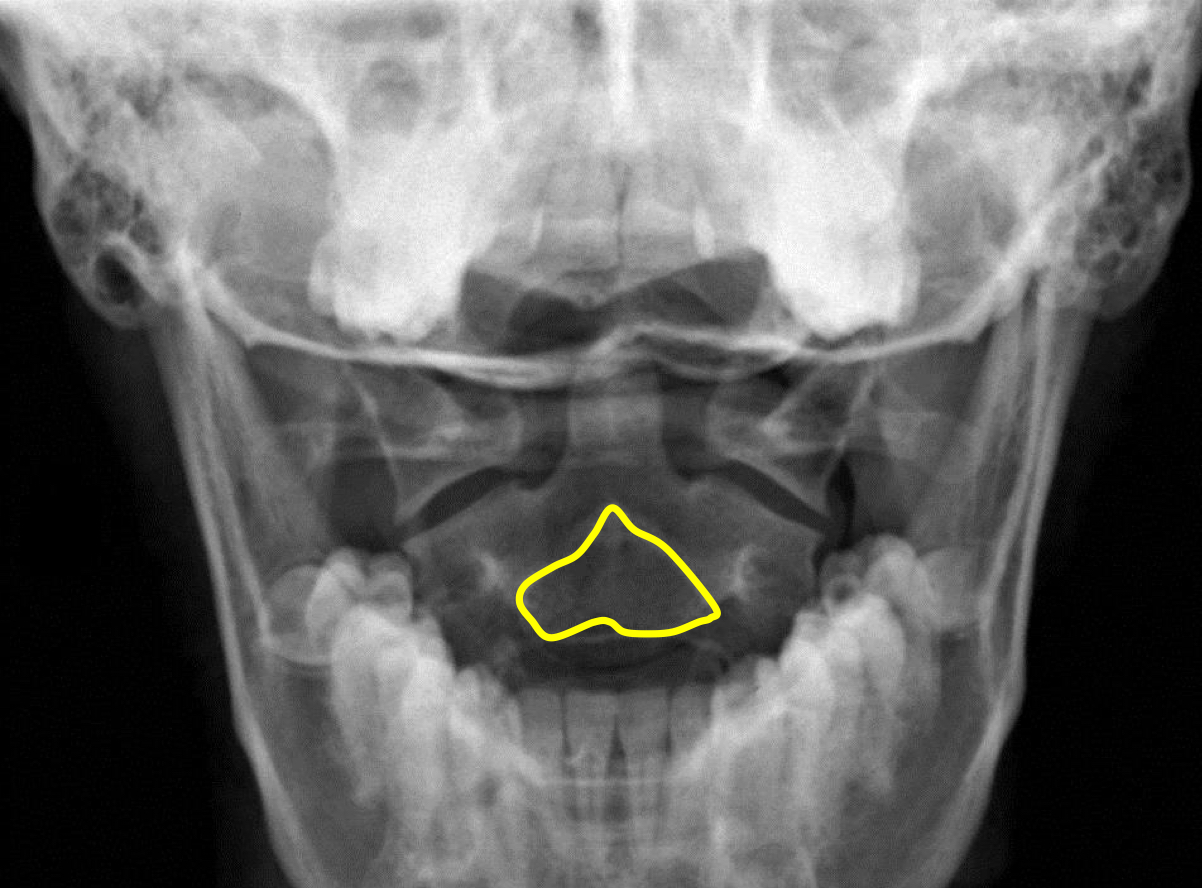

What view is this?

APOM

What is this?

Odontoid Process

What is this?

C2 Spinous Process

What is this?

C2 Pedicle Shadows